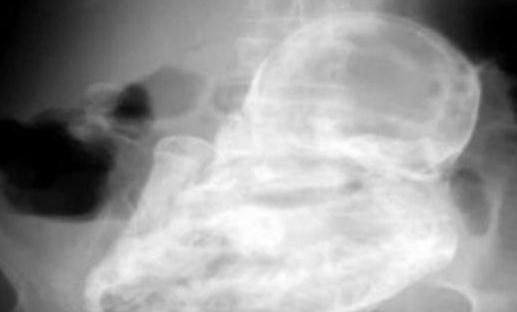

这个孕妇是位82岁的老太太,她因剧烈的腹泻而到该医院就诊。在全面的临床检查之后,医生确定她的腹部并没有结石或肿瘤。

不过,接下来的发现却让所有人吓了一大跳——老太太的子宫外竟然有个未发育的胎儿,但已经死亡了近40年。

这个“石化胚胎”是怎么形成的呢?医生解释称:“由于胚胎未在子宫里发育,移动到老妇的腹腔,导致胚胎无法正常生长,因而钙化形成石胎。”